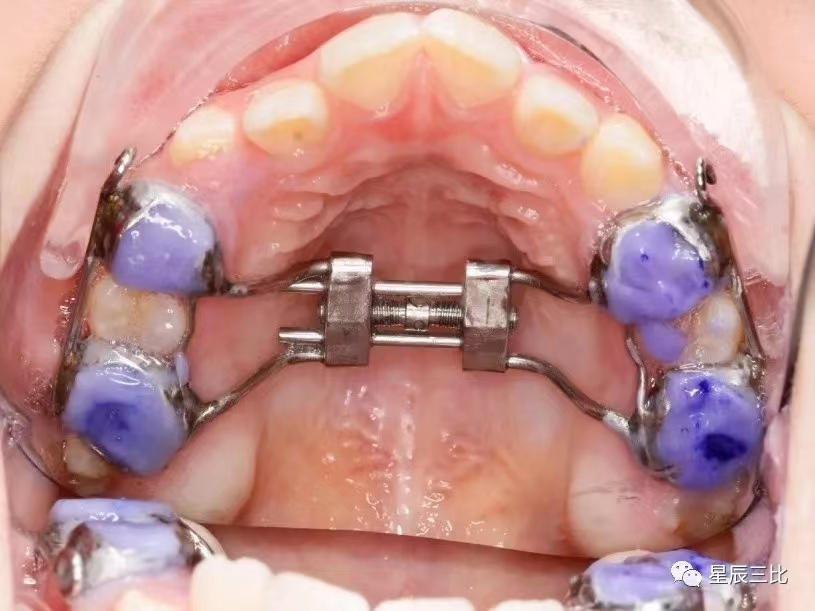

乳牙期及替牙期若出现前牙反牙合,牙弓过窄,面部发育不足,不良习惯等情况时同样需要矫正,只是矫正方法较传统矫正技术略有不同

1、口腔正畸目前开展的项目有:错颌畸形的系统规范的检查、诊断测量分析,各类错颌畸形的正畸治疗,直丝弓固定自锁托槽矫正、种植支抗钉技术、隐形矫正(隐适美、时代天使);